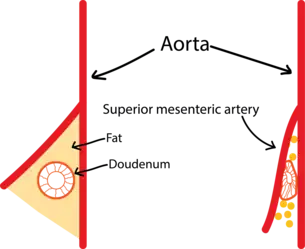

Ultrasound showing SMA syndrome[18] A diagram of a healthy mesenteric angle.

A diagram of a healthy mesenteric angle. A diagram of a compressed duodenum due to a reduced mesenteric angle.

A diagram of a compressed duodenum due to a reduced mesenteric angle.